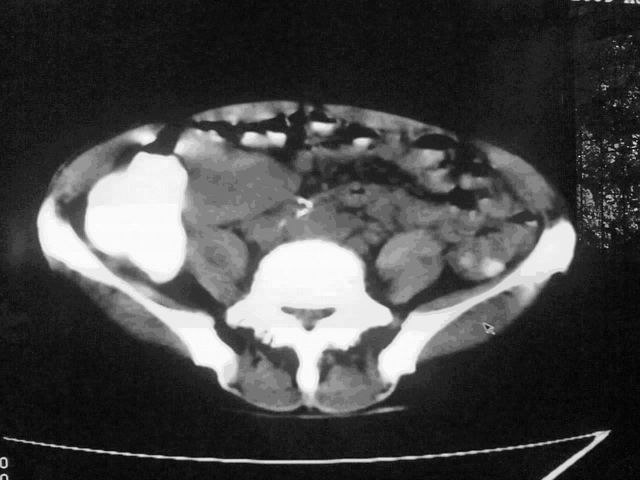

我这个考考大家眼力,看看是升结肠ca还是降结肠ca

下面的是4小时后的,

伪影太多,考虑降结肠癌伴肝转移,胆囊炎

伪影太多,考虑升结肠癌伴肝转移,胆囊炎

结肠占位并肝及腹膜后淋巴结转移。